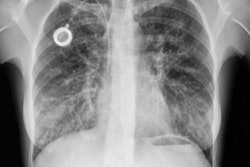

The Archimedes VBN System combines fused fluoroscopy, real-time bronchoscopy, and virtual bronchoscopic navigation for 3D views and access to nodules anywhere in the lung, with the ability to avoid major blood vessels through vessel mapping.

Specifically, the study showed that using Archimedes to guide bronchoscopic transparenchymal nodule access (BTPNA) enabled a sampling yield of 90.2% and a biopsy yield of 86.3%, while the sampling yield across both BTPNA and guided transbronchial needle aspiration was 93.9%.